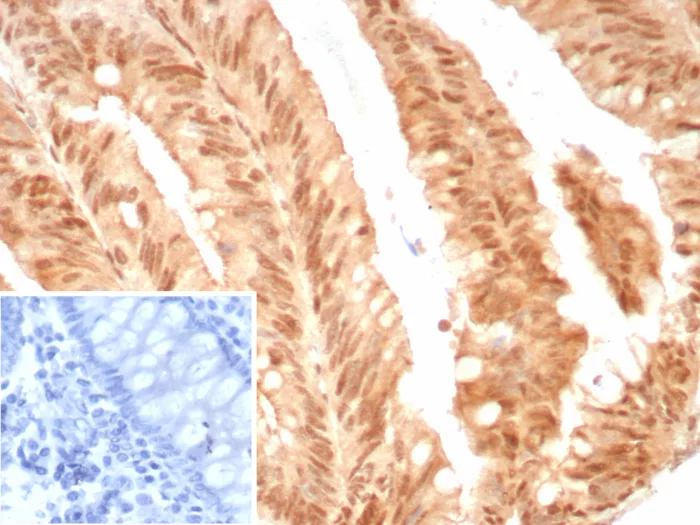

Immunohistochemistry (IHC)

1-2ug/ml

30 min at RT. Staining of formalin-fixed tissues requires heating tissue sections in 10mM Tris with 1mM EDTA, pH 9.0, for 45 min at 95°C followed by cooling at RT for 20 minutes